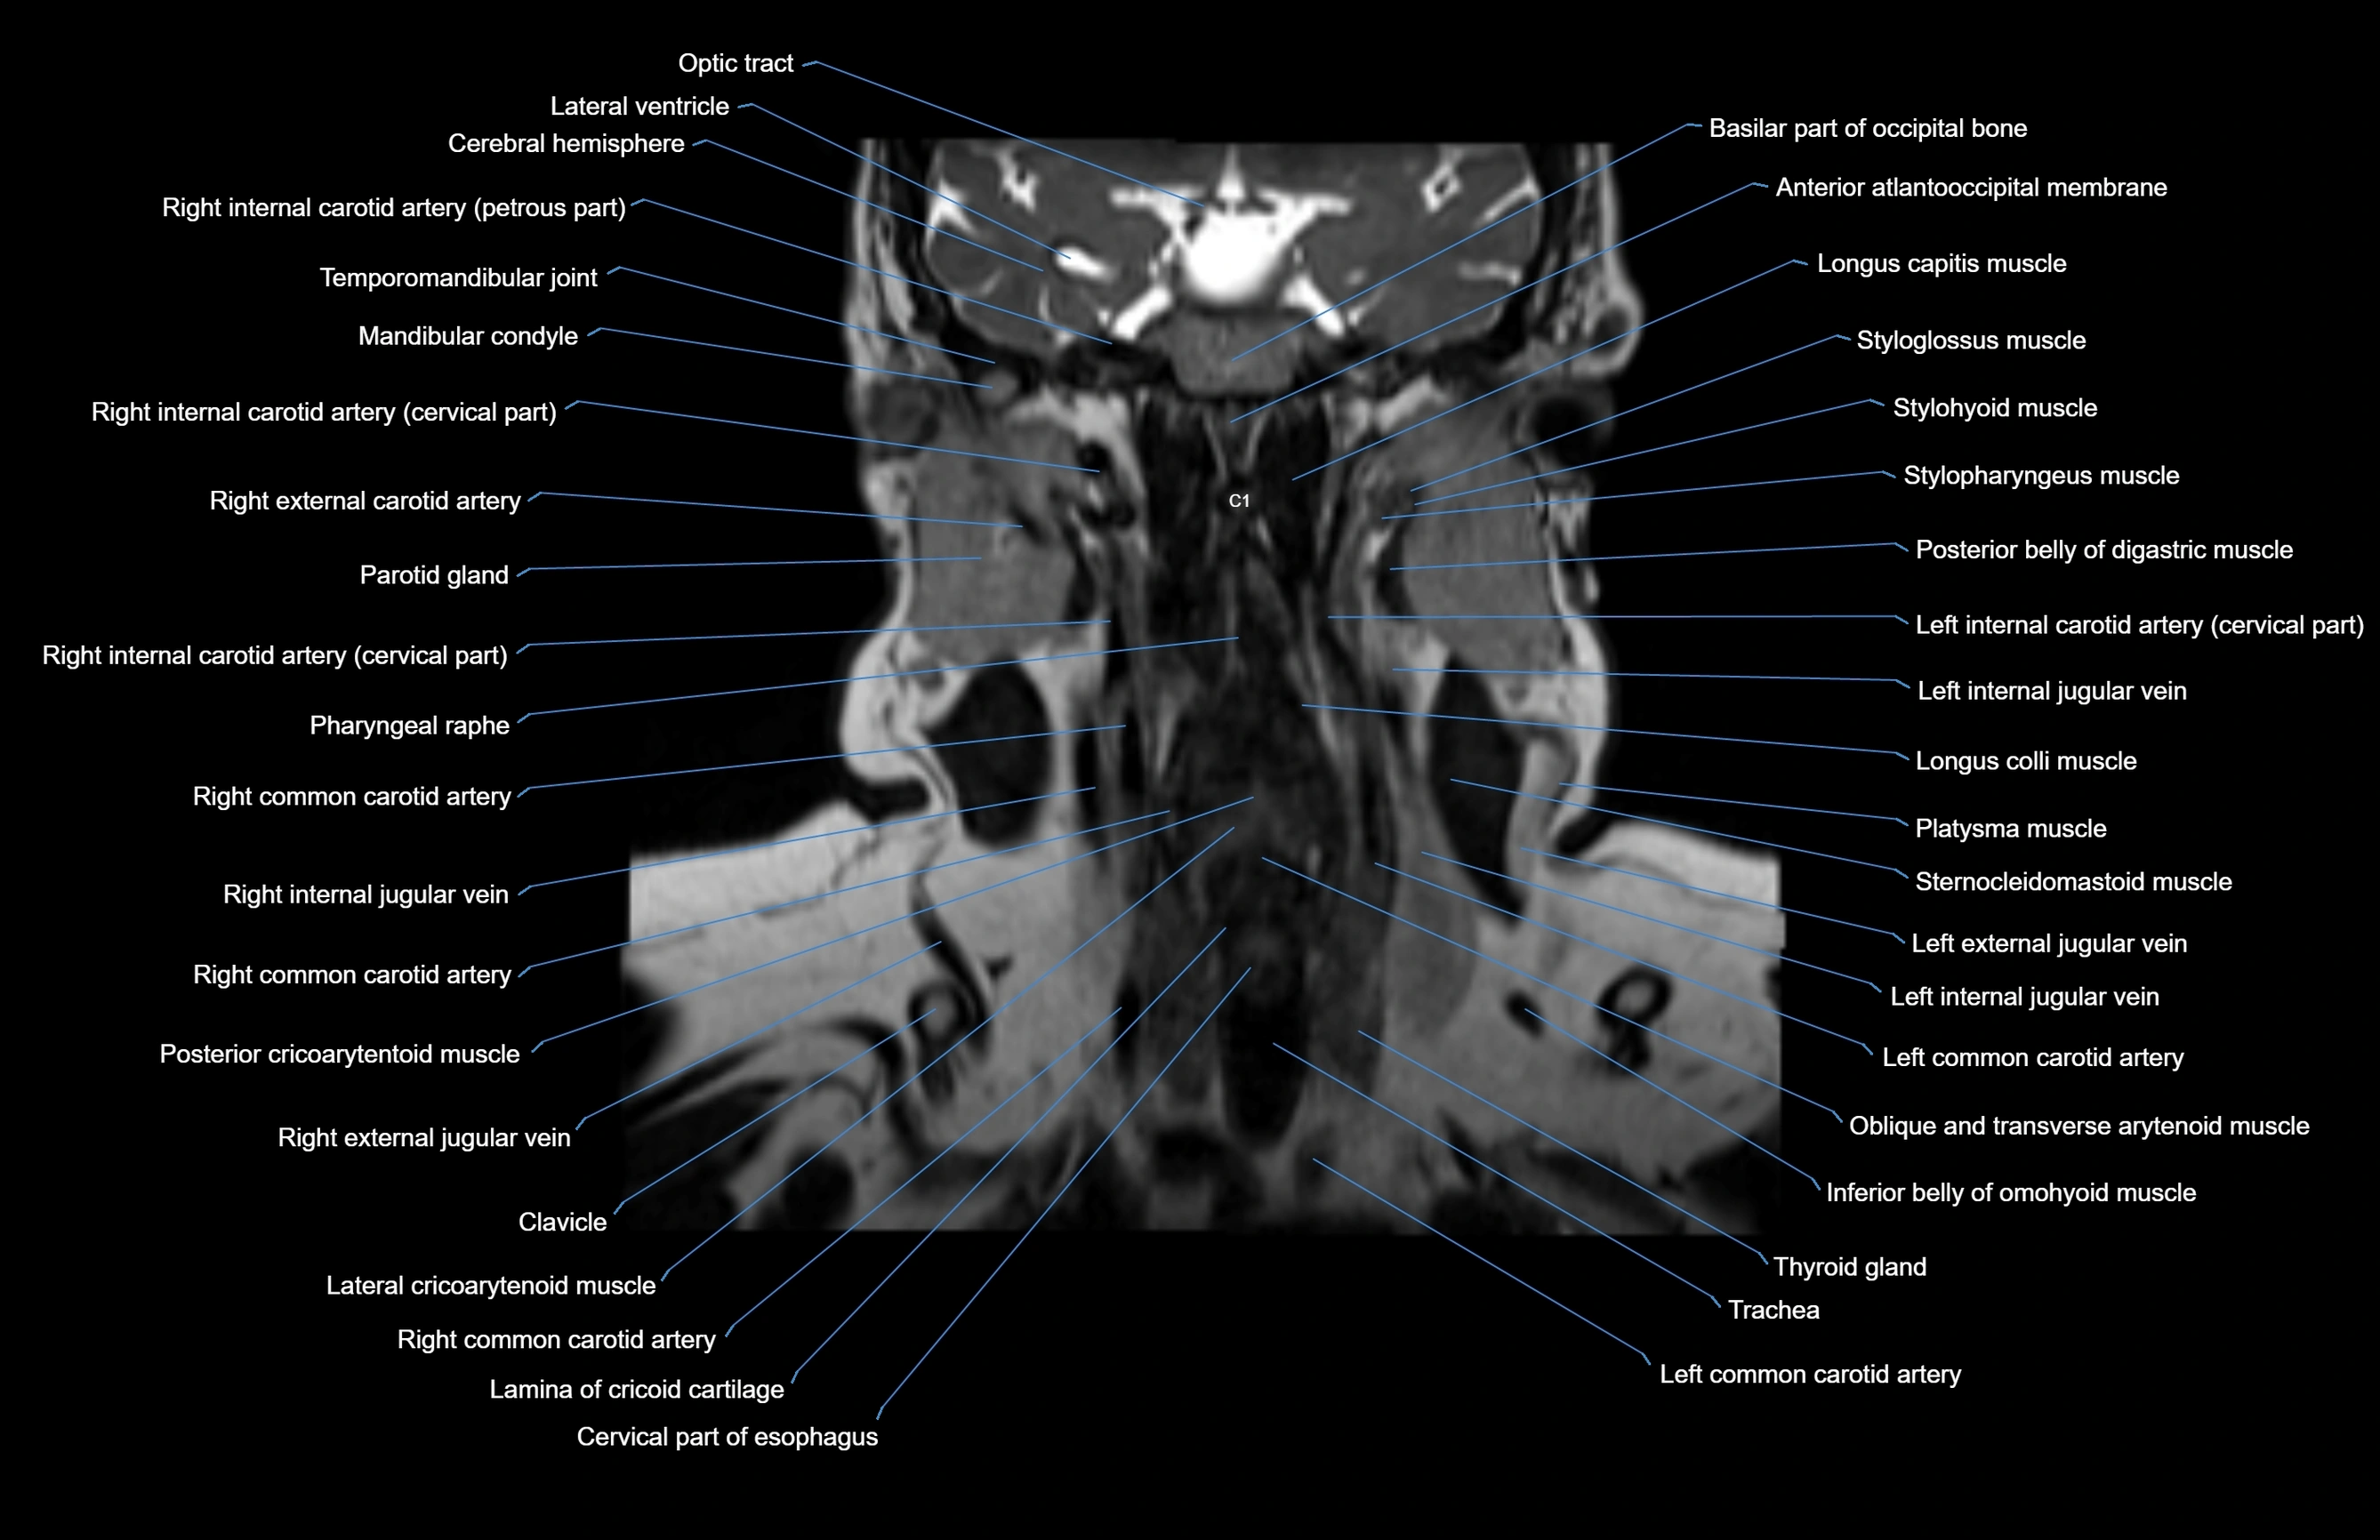

- Anterior atlantooccipital membrane

- Anterior belly of digastric muscle

- Clavicle

- Common carotid artery

- External jugular vein

- Inferior belly of omohyoid muscle

- Inferior longitudinal lingual muscle

- Lateral cricoarytenoid muscle

- Left common carotid artery

- Longus capitis muscle

- Longus colli muscle

- Mandibular condyle

- Parotid gland

- Pharyngeal raphe

- Platysma muscle

- Posterior belly of digastric muscle

- Sternocleidomastoid muscle

- Styloglossus muscle

- Stylohyoid muscle

- Stylopharyngeus muscle

- Thyroid gland

- Trachea